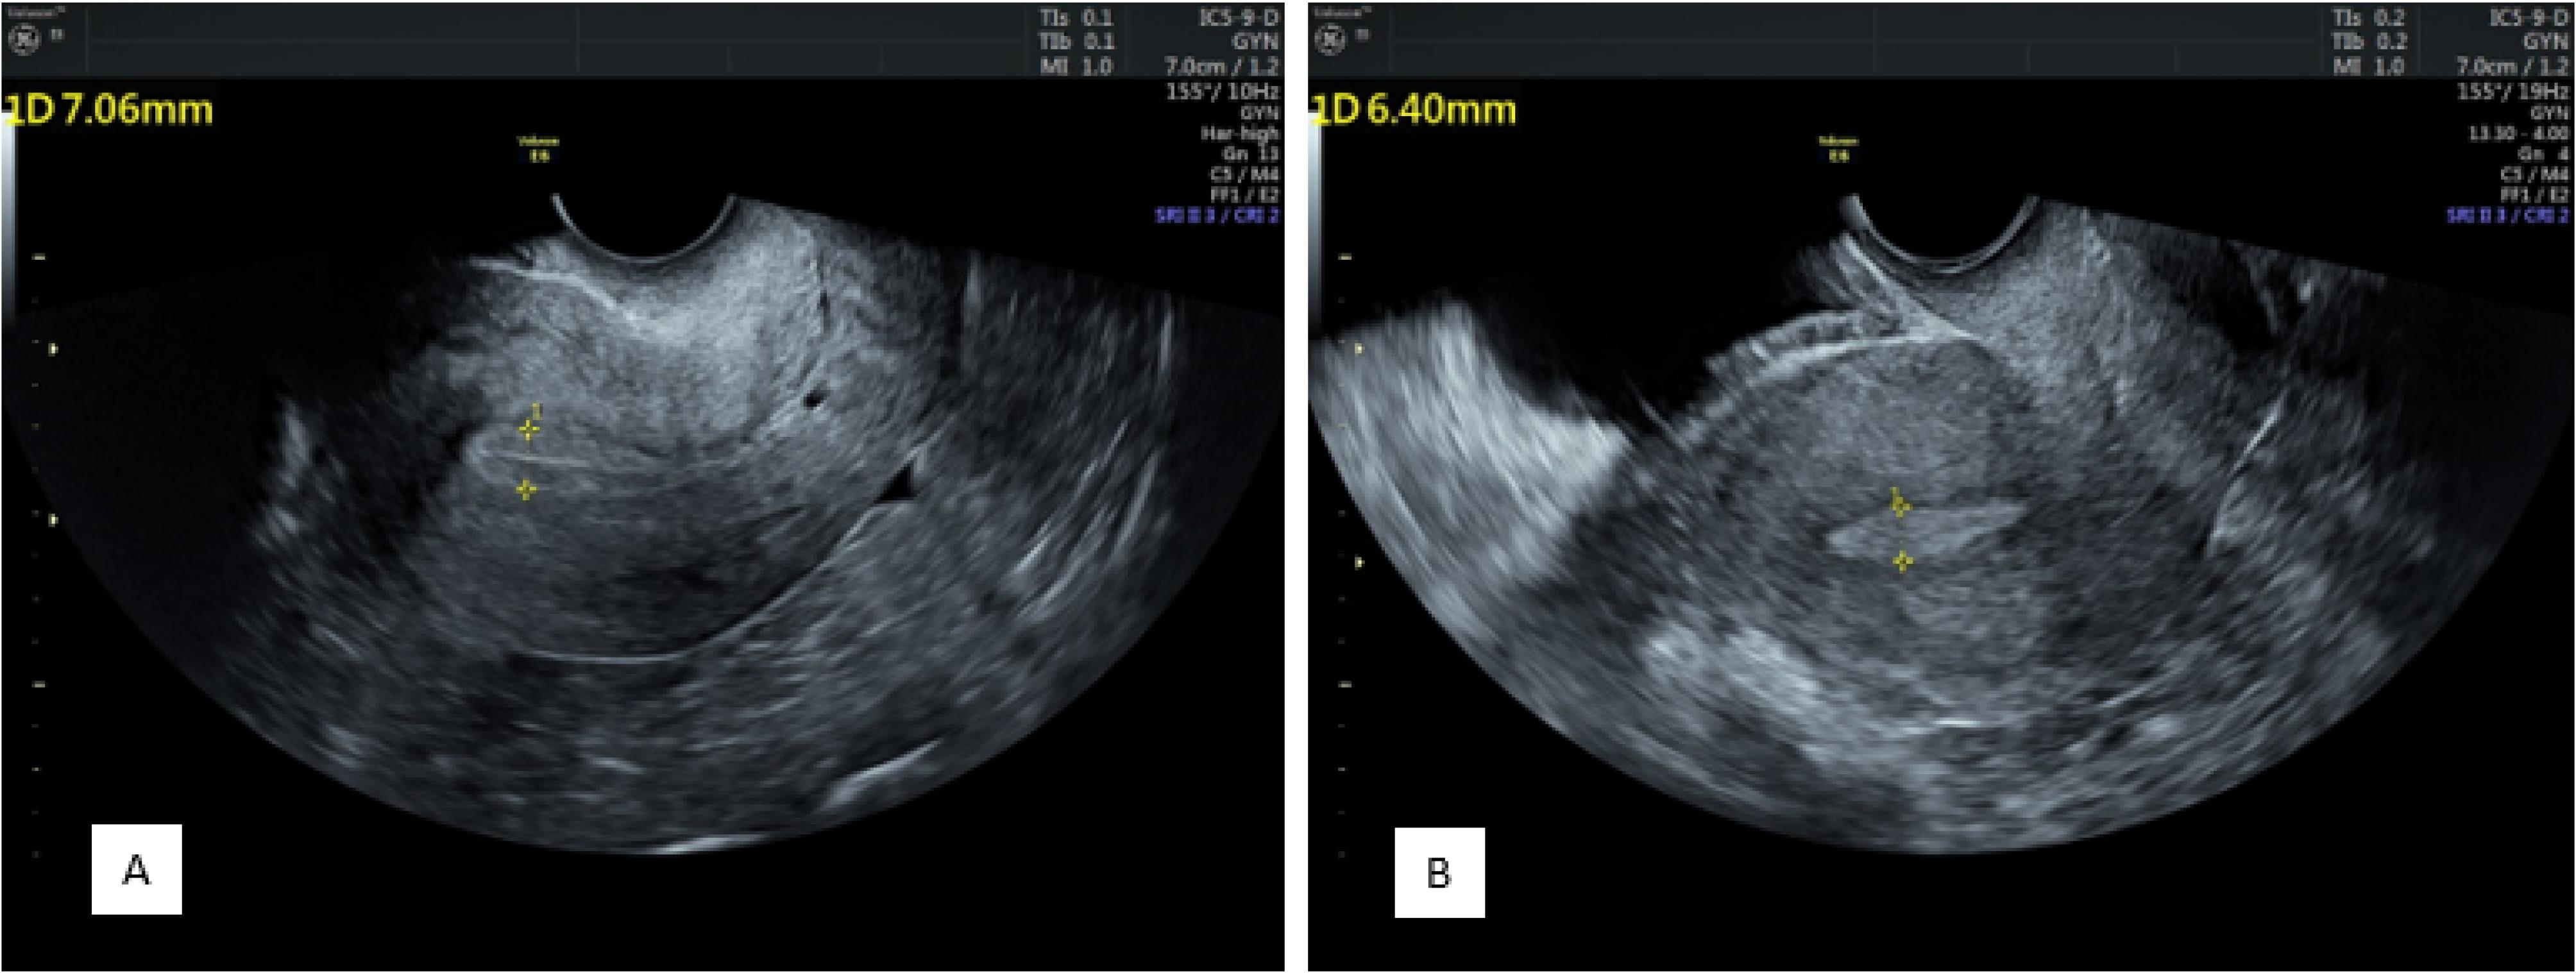

Endometrial Zone III Vascularity

According to the comparison results related to zone III vascularity distribution in patients before progesterone administration, multifocal distribution was observed in 166 patients, and sparse distribution was found in 34. After administration, multifocal distribution and sparse distribution were detected in 111 and 89 patients, respectively (P = 0.001).

As regards zone III vascularity distribution before progesterone administration in the positive pregnancy group, multifocal distribution and sparse distribution were found in 76 and 5 patients, respectively. In the negative pregnancy group, multifocal distribution was observed in 90 patients, and sparse distribution was detected in 29 patients (P = 0.001).

Concerning zone III vascularity distribution after progesterone administration in the positive pregnancy group, both types of distribution were found in 56 (multifocal distribution) and 25 (sparse distribution) patients, respectively. In the negative pregnancy group, multifocal distribution and sparse distribution were observed in 55 and 64 patients, respectively (P = 0.001, Figure 3).

Figure 3.

Endometrial Zone III Vascularity Distribution Before (A) and After (B) Progesterone 9 Administration Demonstrating a Decrease in Multi-focal Distribution and the Sparse Vascularity Being 10 More Prominent